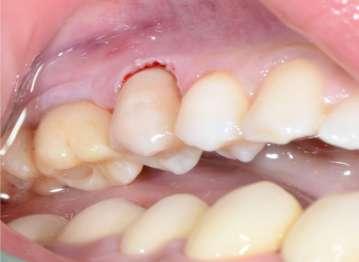

Paziente femmina, 38 anni che presenta carie cervicale dell’elemento 1.5. Gengivectomia con manipolo angolato, tip in zaffiro con diametro di 400 μm, lunghezza 12 mm, 2.4 W, 20 Hz, 120 mJ E per impulso, potenza di picco 750 W, densità di potenza media 659 W/cm2, densità di potenza di picco 205,860 W/cm2, energia totale 432 J, larghezza impulso 160 μs, distanza tip-tessuto 1 mm, 50% acqua, 50% aria, tempo totale di trafamento 180 sec. Impostazioni dello smalto: manipolo angolato, tip in zaffiro diametro 800 μm, lunghezza 12 mm, totale energia 810 J, ampiezza dell’impulso 160 μs, distanza tip-tessuto 1 mm, 100% acqua, 70% aria, tempo di trafamento totale 180 sec.

Fig. 1 – Cavità su 1.5 Fig. 2 – Particolare della cavità del dente 1.5 Fig. 3 – Preparazione Laser Er:YAG Pluser con lunghezza d’onda di 2940 nm di LAMBDA DoctorSmile, Italia. Fig. 4 – Particolare della cavità dopo gengivectomia Fig. 5 – Particolare della cavità completata dopo la preparazione della dentina Fig. 6 – Restauro finale in composito (Asteria Tokuyama, Japan)